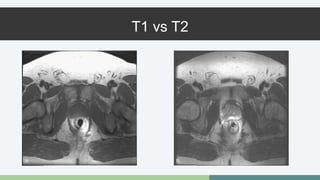

T1 vs T2

Resonancia Magnética •Se usa cuando hay antígeno elevado y biopsia negativa • Se puede utilizar pre o post Qx • Se busca si hay extensión extracapsular • Permite visualizar invasión de la vesícula seminal • T2